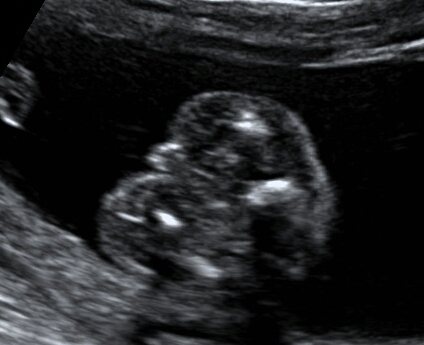

please help me guess the gender of my baby 18weeks scan...i have 2 girls and hoping boy this time...Attachment 31046

hi, yes it is the potty shot taken during my anomaly scan, my doctor said girl, but im really confused because of this shot...and everyone is telling that I'm having boy and I'm really hoping a boy... here is another shot on 15 weeks Attachment 31050